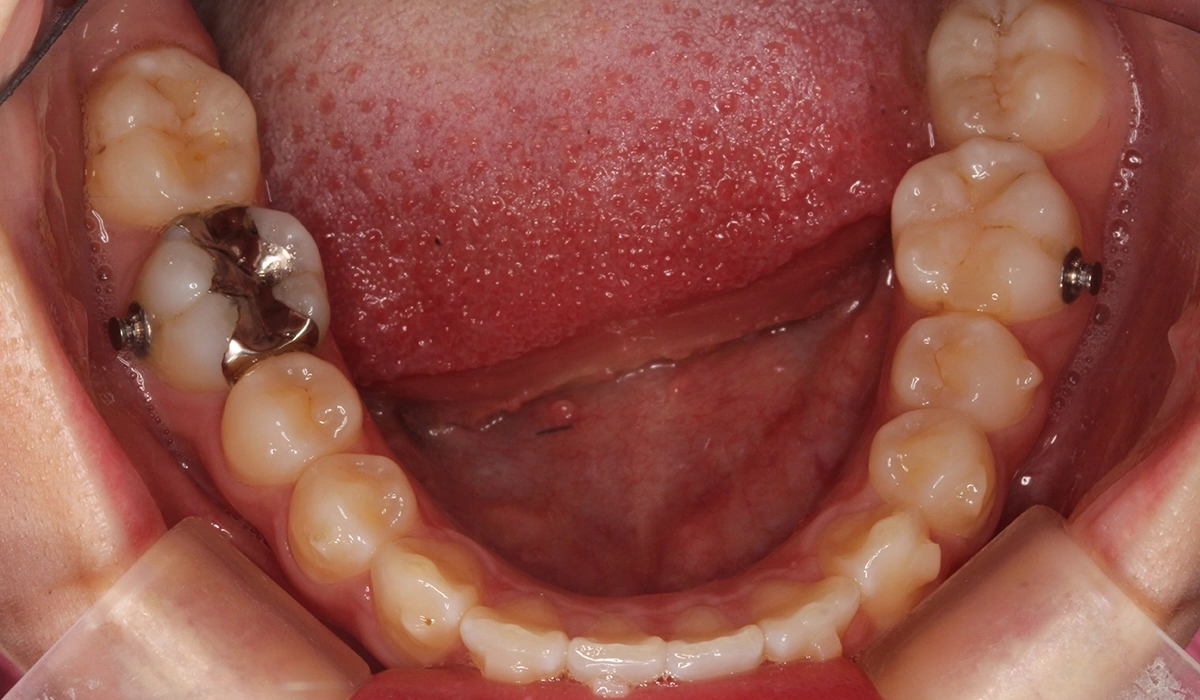

術前:下顎

術後:下顎